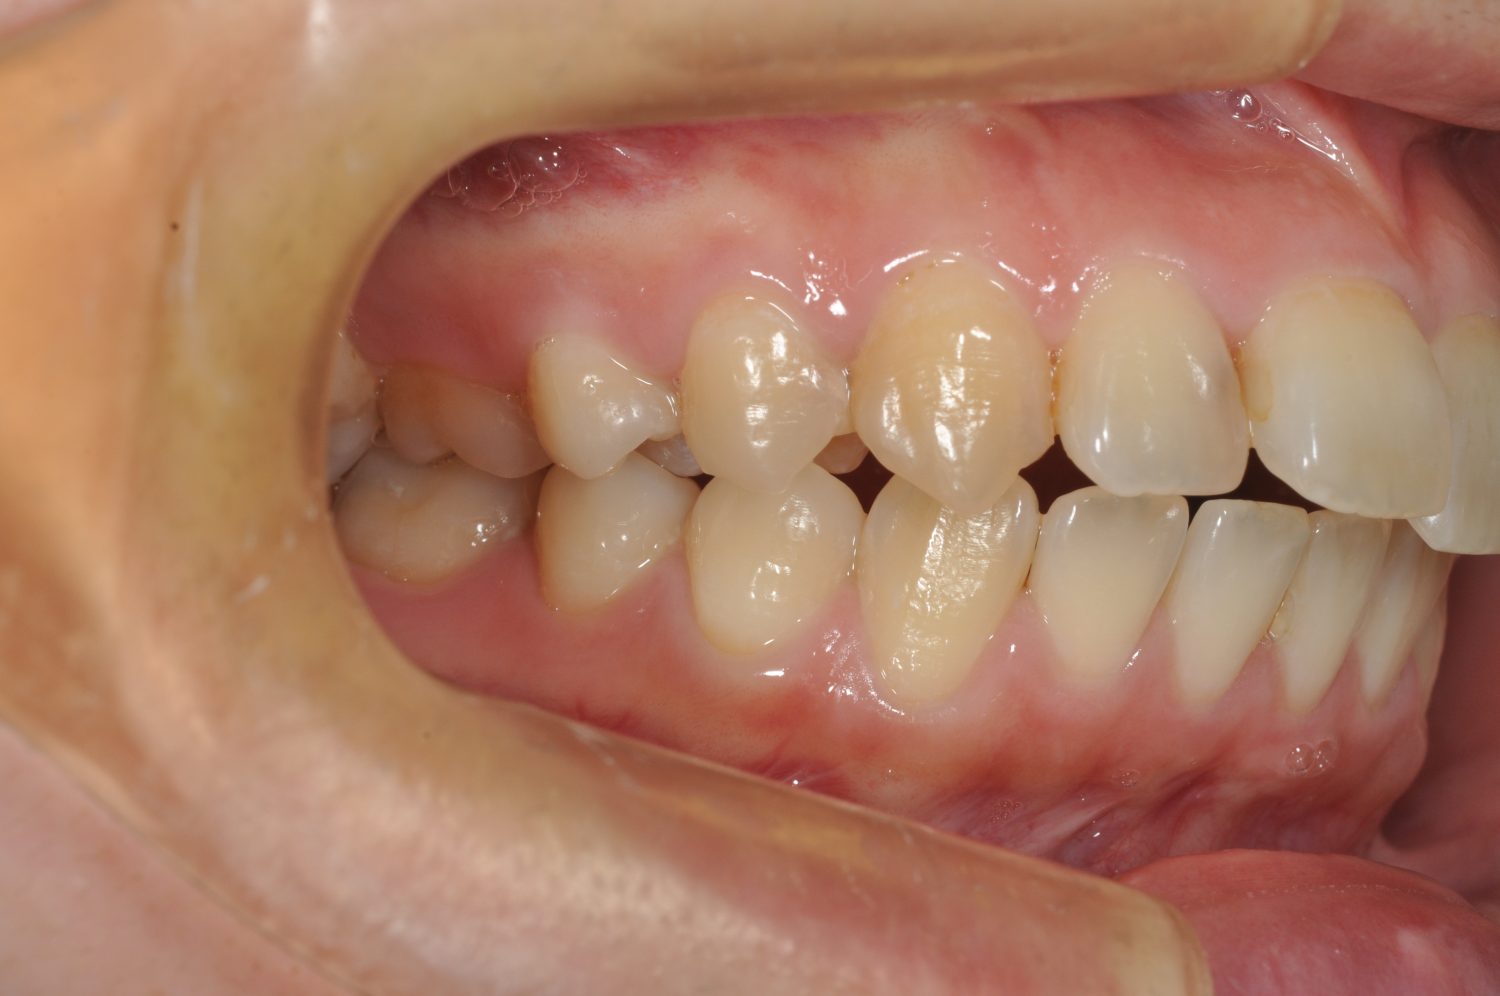

| 主訴 | 前歯の出っ歯を直したい |

| 治療内容 | 上下顎とも標準範囲であるが、上下顎前歯ともに唇側傾斜による、上下顎前突。上顎小臼歯を抜去し配列を行うこととした。 |

| 治療費 | Ⅱ期治療費:770,000円 (税込) 調整料 5,500円 (税込)×23回 保定時:22,000円 (税込) 計 918,500円 (税込) |

| 治療期間 | 2年1ヶ月 |

| 治療回数 | 25回 |

| 想定されたリスク | 矯正器具の装着に伴い、むし歯や歯周病のリスクがありました。また、歯根吸収や歯肉退縮のリスクもありました。 |

上下顎前歯の唇側傾斜による上下顎前突。オーバージェットが大きいため、上顎のみの抜歯で配列を行った。